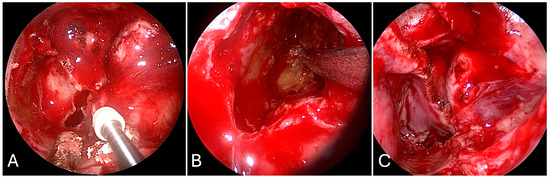

3.4. Transpterygoid

3.4.2. Illustrative Case

3.4.3. Practical Pearls

- Sacrifice of the sphenopalatine artery in the transpterygoid approach precludes an ipsilateral nasoseptal flap.

- Skeletonization of the maxillary nerve leads to the ‘quadrangular space’ and Meckel’s cave.

- Skeletonization of the vidian nerve leads to the lacerum segment of the ICA.

- The contralateral transmaxillary approach may be a useful back up option for lateral petrous pathologies approaching the IAC.